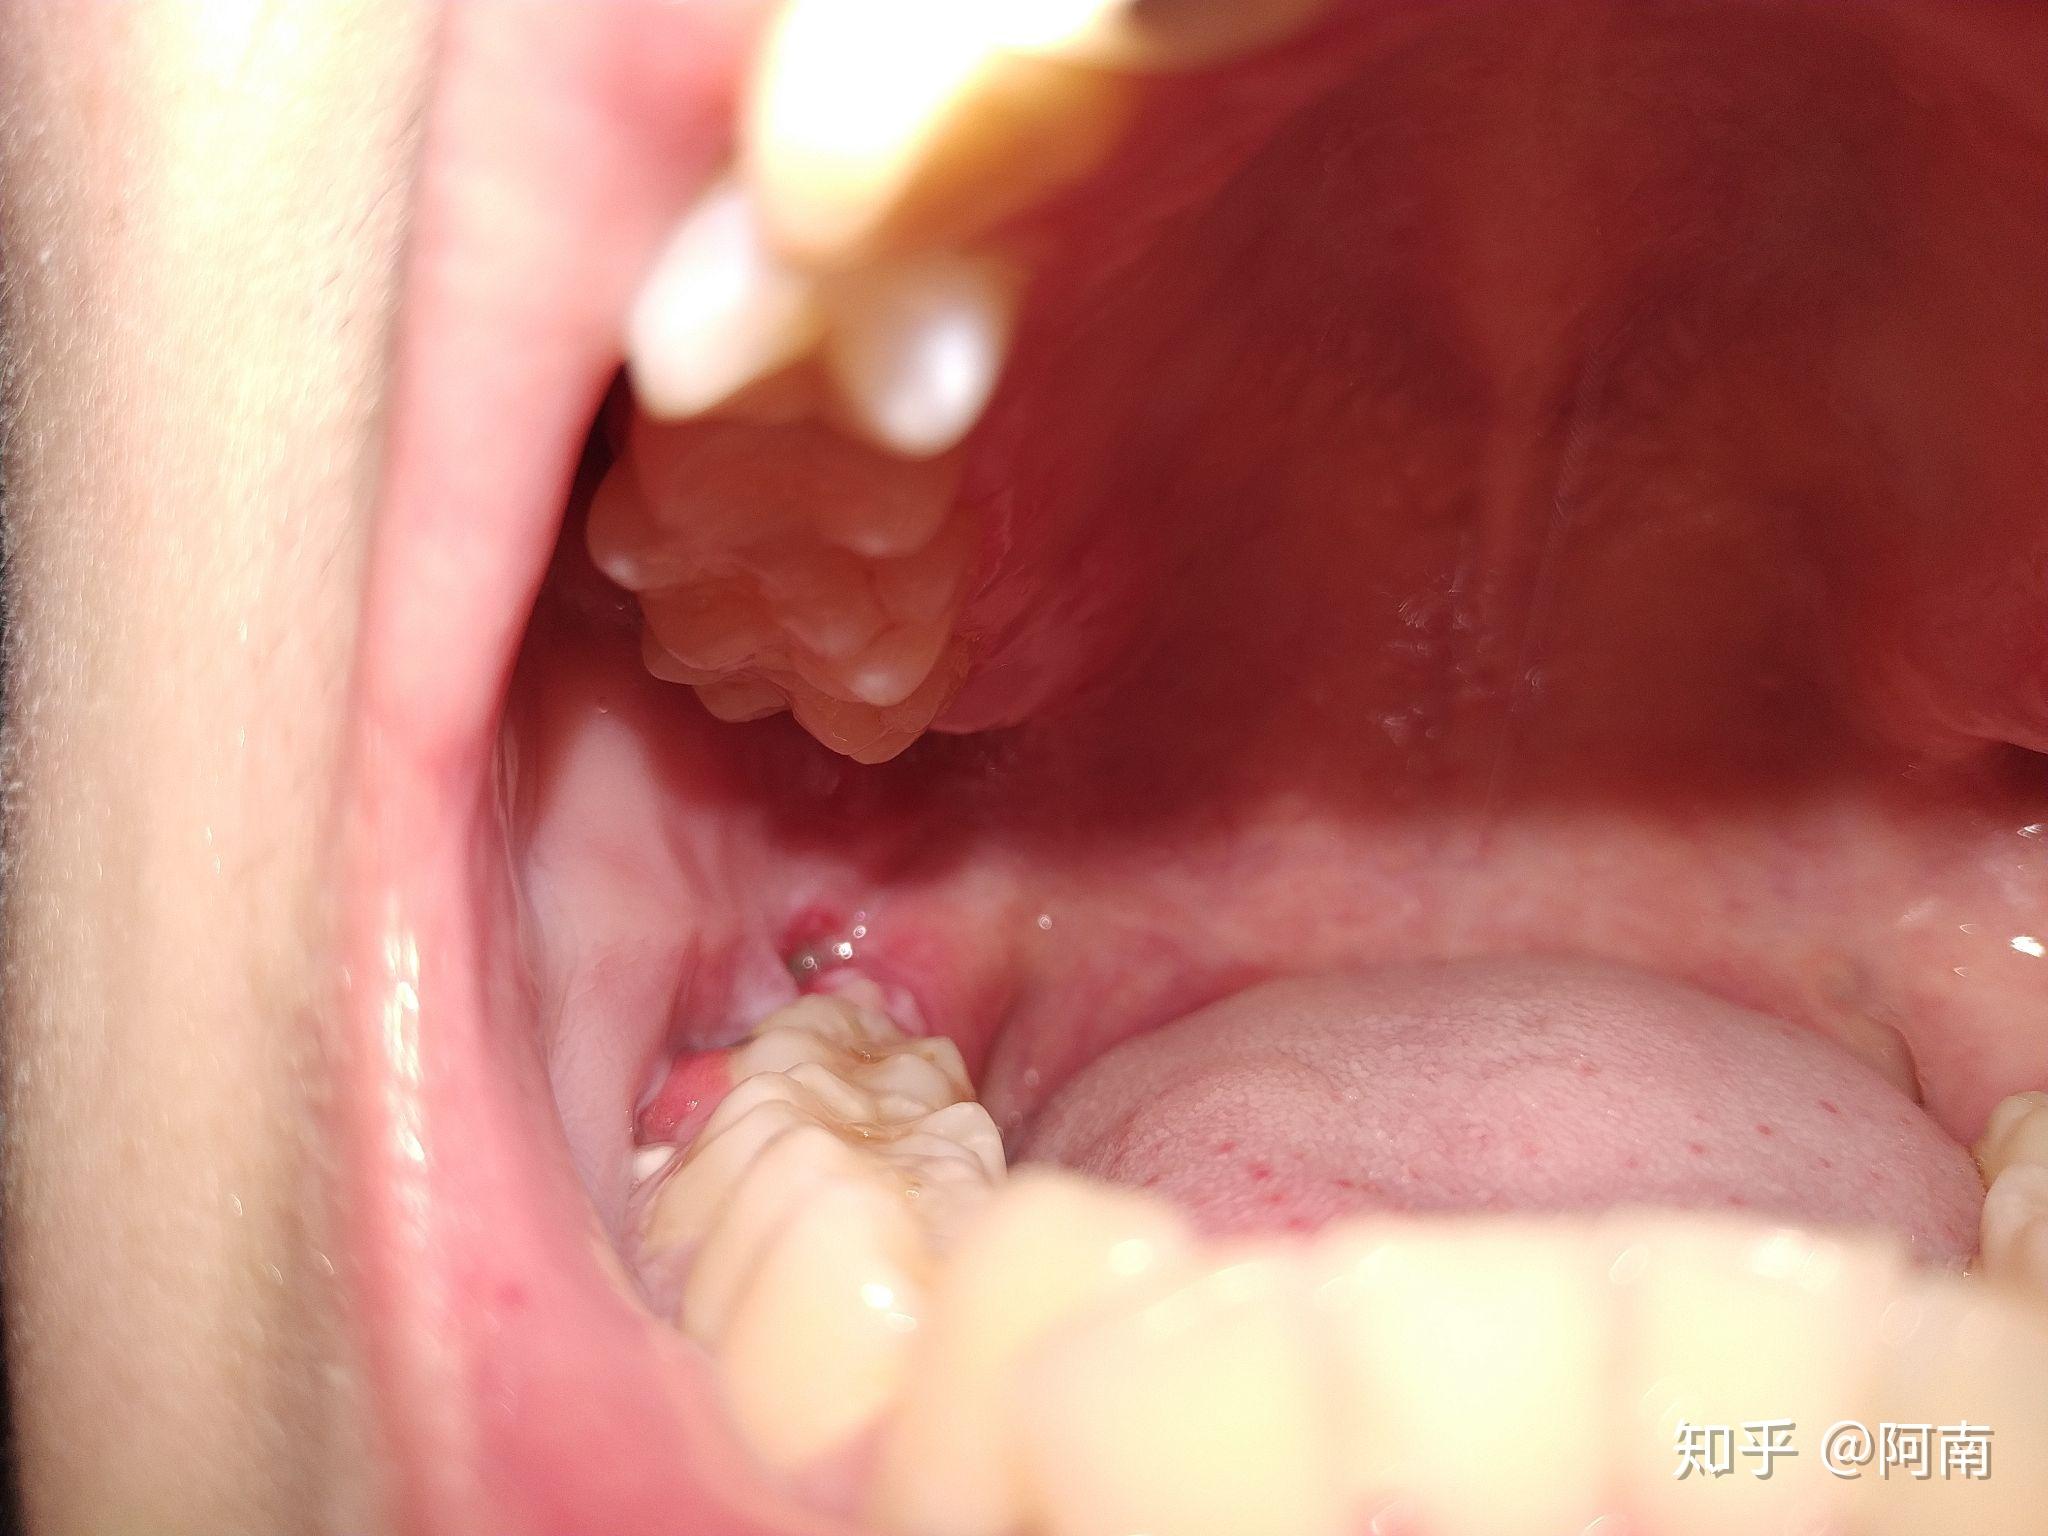

拔智齿恢复记录低位阻生

图片尺寸1080x1440